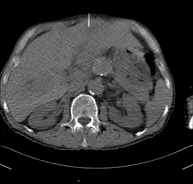

Prueba diagnóstica que consiste en obtener imágenes del abdomen de alta definición anatómica (hígado, vesícula biliar, vía biliar, páncreas, bazo, estómago, intestinos, riñones, estructuras vasculares, vejiga, útero y ovarios, etc.) mediante el empleo de un equipo de TC (Tomografía Computarizada). Dichas imágenes se estudian posteriormente en una estación de trabajo que permite reconstrucciones bidimensionales en diferentes planos del espacio, y también reconstrucciones 3D (volumétricas). La mayoría de estudios requieren el empleo de contraste yodado para mejorar la definición de las imágenes. - TC Pelvis

Prueba diagnóstica que consiste en obtener imágenes bi y tridimensionales del abdomen y de la pelvis de alta definición anatómica (estructuras óseas, estructuras vasculares, hígado, páncreas, vesícula biliar, riñones, glándulas suprarrenales, bazo, intestino delgado y grueso, vejiga, útero y ovarios, próstata y vesículas seminales, uréteres, etc.) mediante el empleo de un equipo de TC (Tomografía Computarizada). La mayoría de estudios requieren el empleo de contraste yodado. - TC Hígado